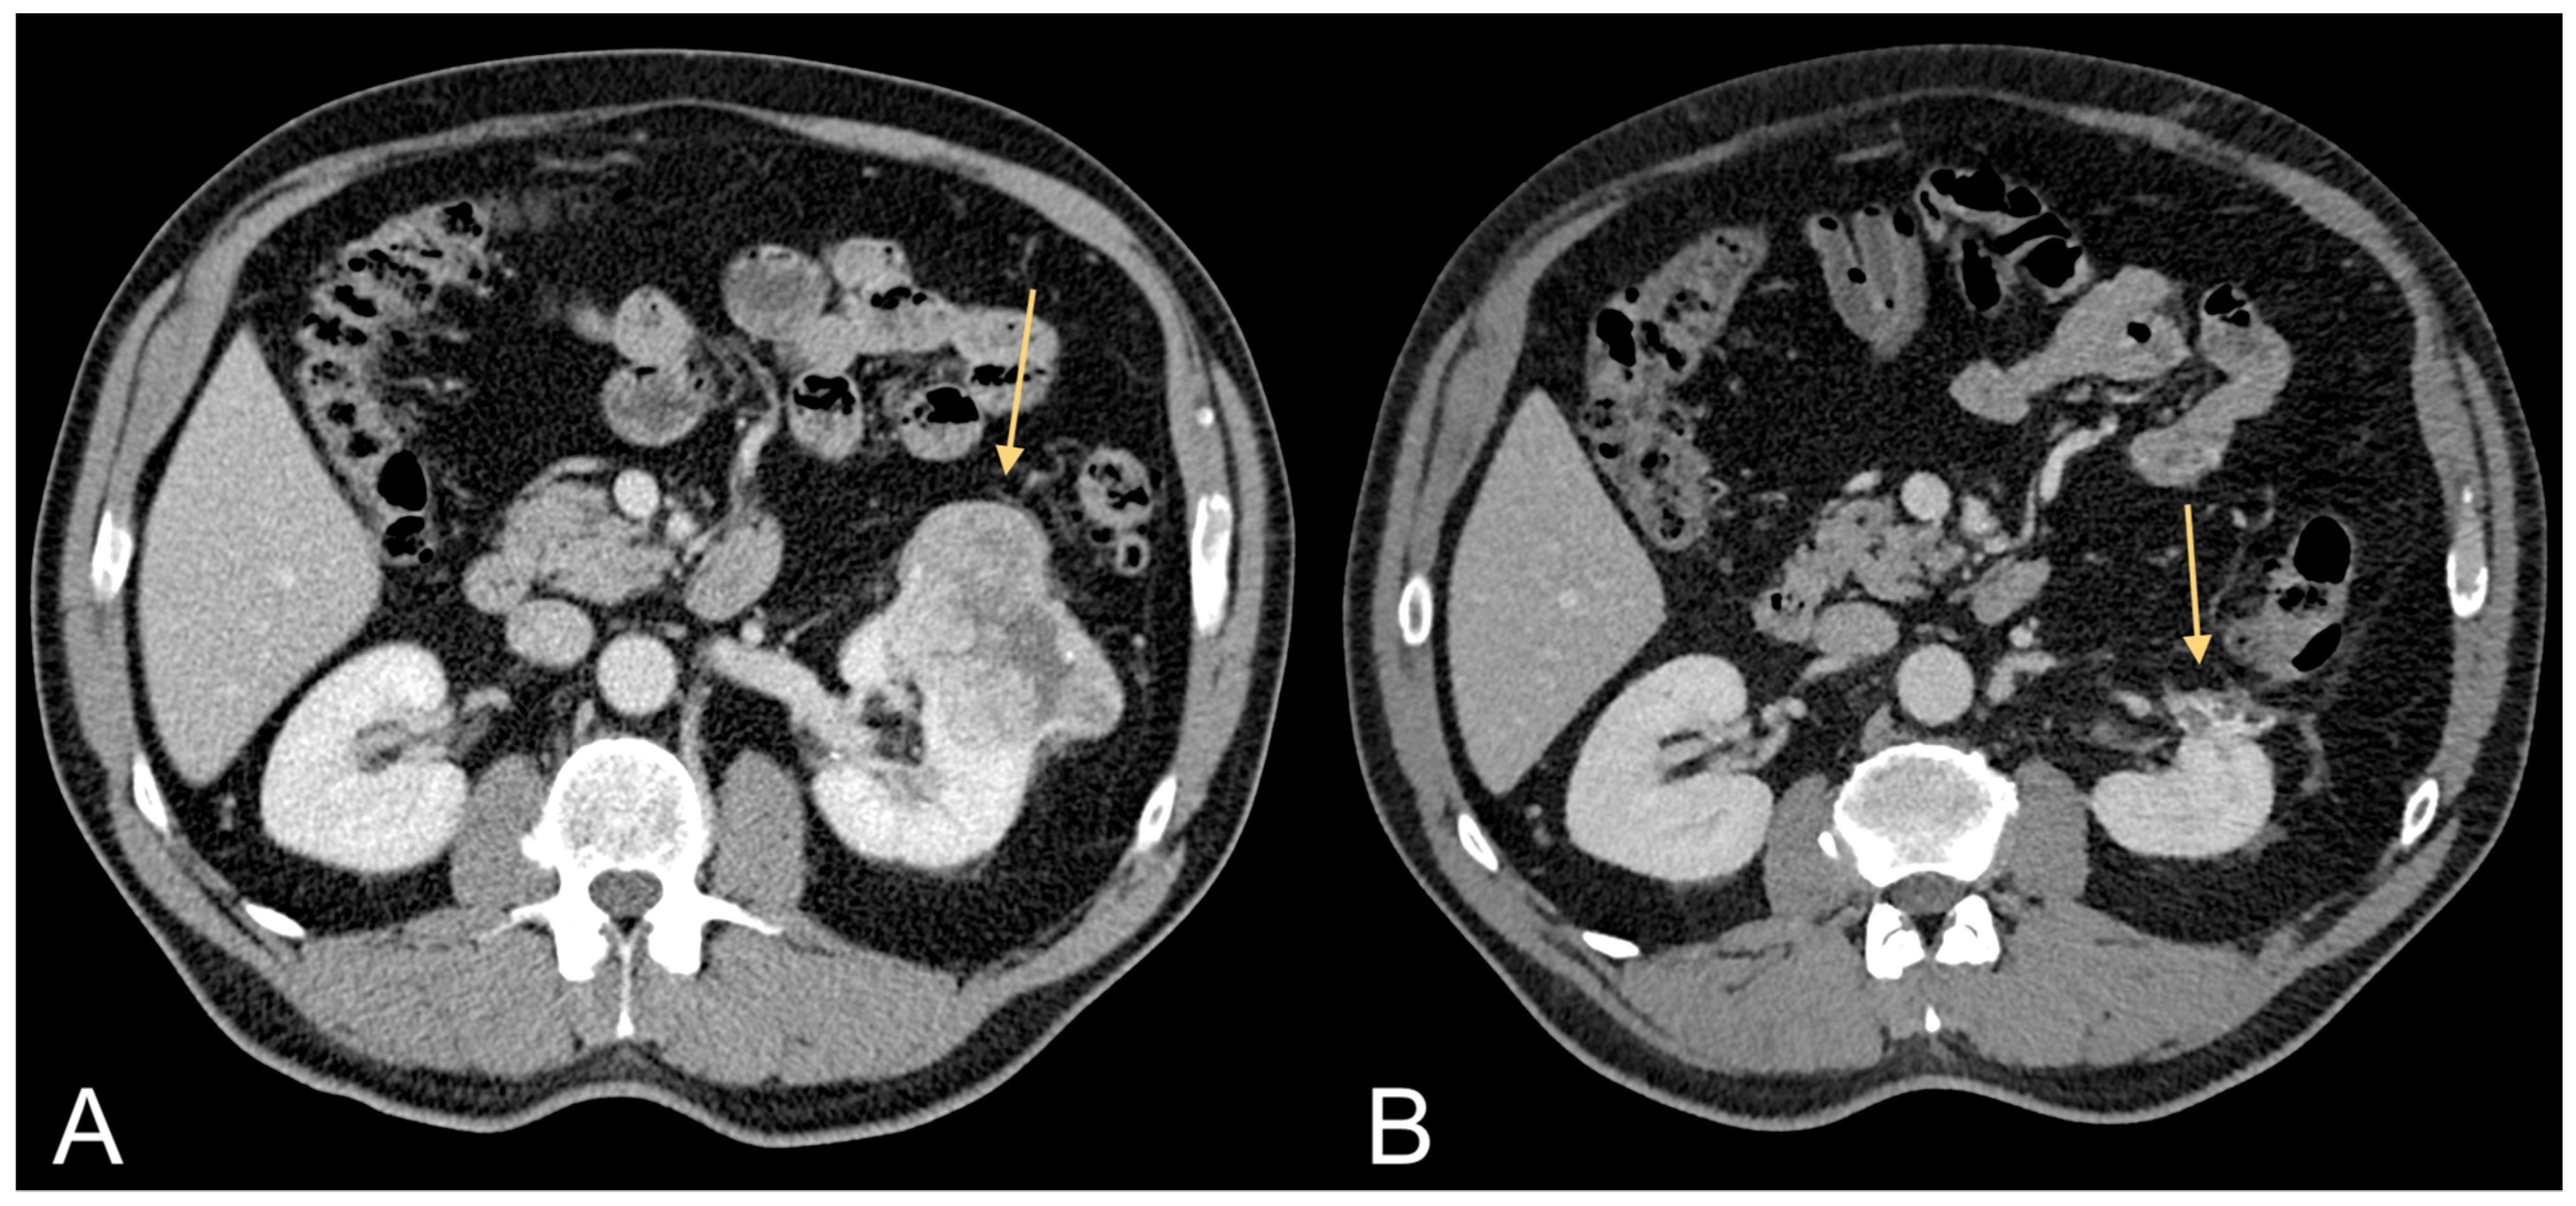

3.6. Visceral Adipose Tissue and Kidney Cancer Risk

- Greco, F.; Cirimele, V.; Mallio, C.A.; Beomonte Zobel, B.; Grasso, R.F. Increased visceral adipose tissue in male patients with clear cell renal cell carcinoma. Clin. Cancer Investig. J. 2018, 7, 132–136. [Google Scholar] [CrossRef]

- Greco, F.; Quarta, L.G.; Grasso, R.F.; Beomonte Zobel, B.; Mallio, C.A. Increased visceral adipose tissue in clear cell renal cell carcinoma with and without peritumoral collateral vessels. Br. J. Radiol. 2020, 93, 20200334. [Google Scholar] [CrossRef]

- Greco, F.; Quarta, L.G.; Bernetti, C.; Grasso, R.F.; van Berge Henegouwen, M.I.; Beomonte Zobel, B.; Mallio, C.A. Composition of Perinephric Fat and Fuhrman Grade in Clear Cell Renal Cell Carcinoma: The Role of Peritumoral Collateral Vessels. Appl. Sci. 2021, 11, 3941. [Google Scholar] [CrossRef]

| Greco et al. (2018) [38] | 10 ccRCC patients | CT | 3 cm above the lower margin of L3 | 35 male patients of control group 10 male ccRCC patients | Significative statistical difference between ccRCC patients and control group (p = 0.015). |

| Greco et al. (2018) [39] | 106 ccRCC patients | CT | 3 cm above the lower margin of L3 | 35 male patients of control group 106 male ccRCC patients | Significative statistical difference between ccRCC patients and control group (p = 0.004). |

| Greco et al. (2020) [40] | 13 pRCC patients 13 chRCC patients | CT | 3 cm above the lower margin of L3 | 35 male patients of control group 26 male nccRCC patients | Significative statistical difference between nccRCC patients and control group (p = 0.008). |